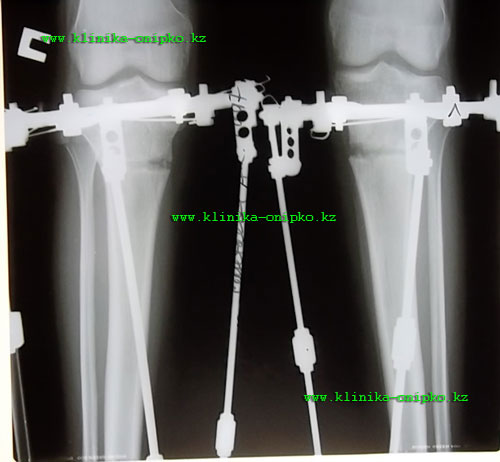

рентгеновские снимки на 11- ый день после операции. Кости выровнены, вышла на фиксацию!